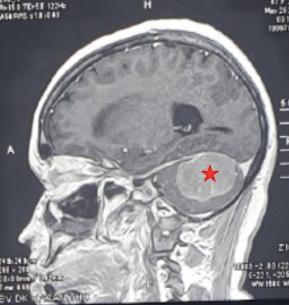

![]() |

Hình MRI khối trước phẫu thuật |

Kết quả chụp cắt lớp não (CT scanner sọ não), Chụp cộng hưởng từ não (MRI) phát hiện có khối choán chỗ nội sọ vùng hố sau bên (P). Đây là một khối u nằm ở vị trí khó tiếp cận, gần với các cấu trúc mạch máu thần kinh quan trọng cũng như có nhiều mạch máu nuôi u nên việc điều trị cho bệnh nhân gồm 2 giai đoạn: Đầu tiên bệnh nhân được chụp mạch máu não số hóa xóa nền để đánh giá hệ thống mạch máu liên quan khối u cũng như tắc mạch nuôi khối u có chọn lọc, nối tiếp là vi phẫu thuật bóc khối u. Ê kíp cắt bỏ hoàn toàn khối u, gỡ dính thành công toàn bộ khối u vào các cấu trúc mạch máu thần kinh quan trọng.